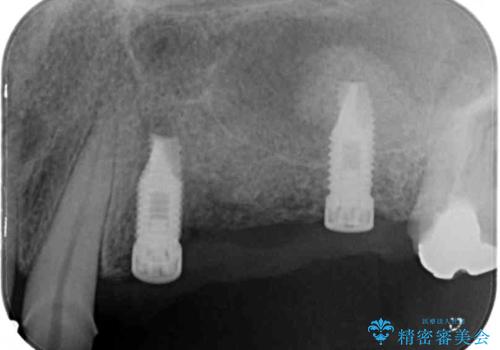

インプラントを埋入するために必要な骨の高さがなかったため、上顎洞底の粘膜を挙上しました。

手術後は処置部に痣や腫脹が出現したり、痛みが出たりしましたが、補綴治療後は咬み合わせが安定し、大変満足していただきました。